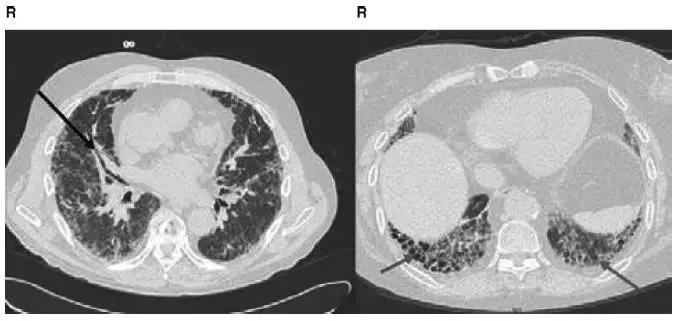

图4-24 Ⅱ期结节病CT:显示淋巴结钙化,肺实质浸润

图4-25 Ⅱ期结节病CT:显示沿支气管血管束分布的结节状阴影